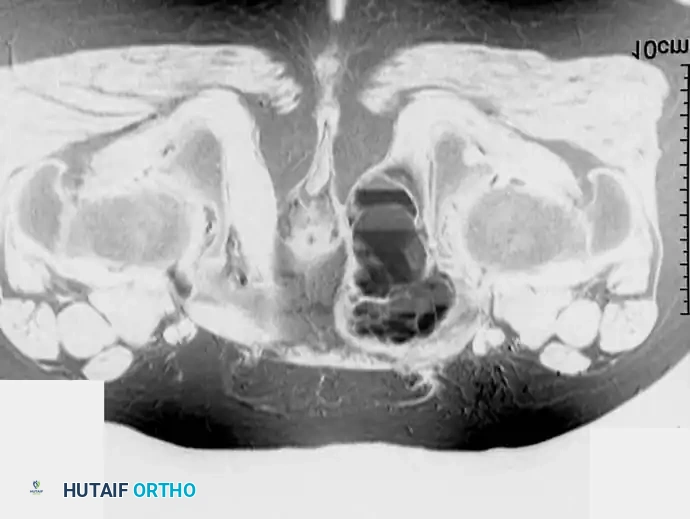

Fig. 20-22: (A and B) Pathological fracture of the right proximal tibia occurring through a large, expansile “brown tumor” of hyperparathyroidism in a 55-year-old woman.